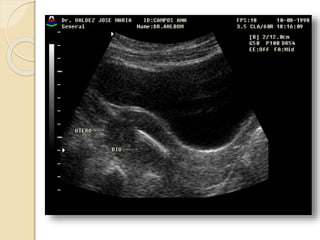

En la ecografía transabdominal el útero

se encuentra entre la vejiga distendida

por delante y el recto por detrás.

El cérvix generalmente se ubica en la

línea media, pero el fondo del útero

comúnmente se sitúa en forma oblicua a

la derecha o izquierda de la línea media.

Con vejiga distendida: el útero esta en grados

diversos de leve anteversión.

Retroposición uterina: Si todo el útero se inclina

hacia atrás desde un punto de apoyo del cérvix, es

retrovertido.

Si solamente el cuerpo y el fondo están flexionados

posteriormente, es retroflexión.